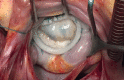

Rheumatic heart disease (RHD) remains the most common cardiovascular disease in young adults and adolescents in need of heart surgery in low- and middle-income countries (LMICs). The mean age of patients is 20-25 years, often much younger. By contrast, the few patients with chronic RHD in developed countries present a mean age of around 55 years. It is absolutely fundamental to differentiate these two types of population. Pathology, lesions and surgical methods are different, and the results should not be compared. It is not all the same! A certain enthusiasm for mitral repair has recently surged, with several reports showing excellent results in children and young adults, resulting from the renewed interest of cardiac surgeons, also based on new and modified techniques developed in the meantime. While surgery is easily accessible to patients in developed countries, the situation in LMICs is often dramatic, with countries where there is a complete absence of or few surgical facilities absolutely unable to meet gigantic demands. Many foreign surgical teams conduct humanitarian missions in several of these countries. They are just a "drop of water in the ocean" of needs. In some cases, however, these missions led to the establishment of local teams that now work independently and, in some cases, outperform the foreign teams still visiting.